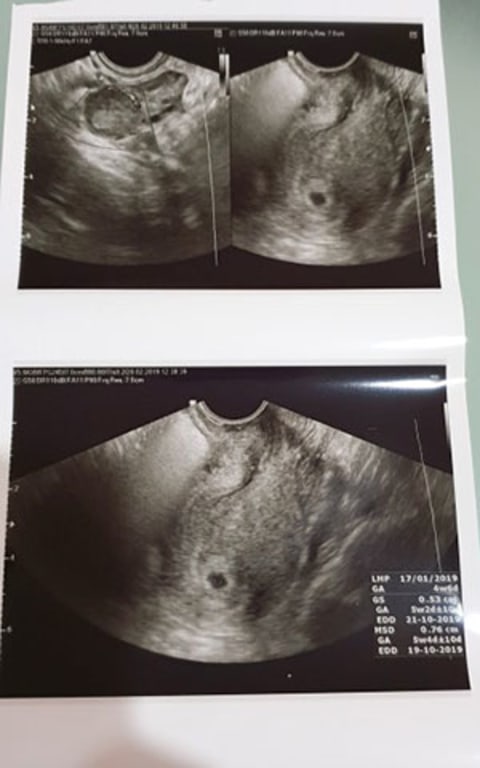

Apa Itu Usg Abdomen ~ Indeed lately has been sought by users around us, maybe one of you. Individuals are now accustomed to using the net in gadgets to view video and image data for inspiration, and according to the name of the post I will discuss about Apa Itu Usg Abdomen. Apa itu usg perut. Komponen komponen alat usg terdiri. Usg abdomen abdominal ultrasound adalah prosedur yang digunakan untuk memeriksa organ organ dalam perut menggunakan sebuah transduser usg probe yang ditempelkan erat pada kulit perut. Gelombang suara energi tinggi dari transduser memantul pada jaringan dan membuat gema. Usg abdomen menghasilkan gambar dari organ dan struktur lain di daerah abdomen perut. Tranduser adalah komponen usg yang ditempelkan pada bagain tubuh yang akan diperiksa. Organ yang dapat dievaluasi usg abdomen. Gema ini dikirim ke komputer yang membuat citra gambar yang disebut. Karena itu usg dapat digunakan untuk mendeteksi perubahan organ jaringan dan pembuluh darah atau mendeteksi massa abnormal seperti tumor. Terdapat 3 jenis usg yang umumnya digunakan yaitu. Prosedur pencitraan dengan menggunakan teknologi gelombang suara berfrekuensi tinggi untuk memproduksi gambar organ dalam perut dengan menggunakan alat sensor probe dan ditampilkan melalui monitor. Usg eksternal usg jenis ini dilakukan dengan menggerakkan alat pemindai probe pada permukaan kulit pasien. Oleh karena itu tindakan ini tergolong aman termasuk bagi ibu hamil. Apa kegunaan usg perut. Doktersehat com apa itu ultrasonografi usg. Usg internal usg internal dilakukan dengan memasukkan probe ke dalam vagina atau anus pasien. Pada usg terdapat sebuah alat yang disebut dengan tranduser yang berfungsi untuk mengirimkan dan menerima kembali gelombang suara yang bervariasi dari. Usg abdomen dapat digunakan untuk mengevaluasi organ berikut. Untuk memeriksa jika terdapat kelainan organ hati ginjal limpa empedu dan pankreas. Ultrasonografi adalah teknik pencitraan non invasiv yang menggunakan gelombang suara frekuensi tinggi lebih besar dari 20 kilohertz khz.